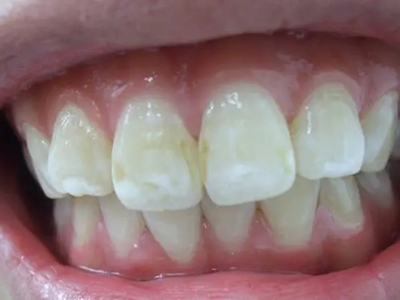

牙釉质发育不全牙齿白斑图

牙釉质发育不全患者可以仅仅出现牙齿色泽和透明度的改变,形成白垩色釉质,即类似于牙齿上有白斑,此时牙冠形态通常较完整。